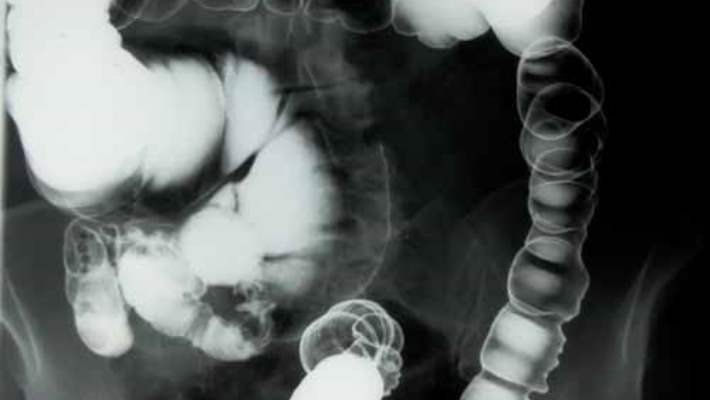

Baryumlu lavman kalın bağırsaktaki (kolon) anormallikleri ya da değişiklikleri tespit etmek için kullanılan özel bir röntgendir. Baryumlu lavman muayenesinin iki türü vardır:

- Tek kontrastlı baryumlu lavman. Tek kontrastlı baryumlu lavman, kolonun iç yüzeyinin metalik bileşik baryum içeren bir solüsyon ile kaplanmasıyla başlar. Bu, doktorunuzun; kolonun şeklinin net bir siluetini ve durumunu görebilmesini sağlar.

- Hava kontrastlı (çift kontrastlı) baryumlu lavman. Hava kontrastlı baryumlu lavman esnasında ise baryum tabakası kolonun iç yüzeyini kapladıktan sonra kolonunuza hava verilir. Hava; kolonunuzu genişletirerek röntgen görüntülerinin kalitesini artırır.

Baryum metalik bir bileşiktir. Baryum çözeltisi kolonunuzun iç çeperini geçici olarak kaplar. Bu da röntgen görüntülerinde kolonunuzun iç çeperinin durumunun ve kolonunuzun şeklinin net bir siluetinin oluşmasını sağlar. Eğer hava kontrastlı (çift kontrastlı) baryumlu lavman uygulanacaksa, kolonun genişletilmesi ve görüntü kalitesinin iyileştirilmesi için rektumunuzdan içeri hava da verilecektir.

Muayene yatağında dönmeniz ve çeşitli pozisyonlarda durmanız istenebilir. Bu bütün kolonunuzun baryum ile kaplanmasını ve radyoloji uzmanının kolonunuzu çeşitli açılardan incelemesini sağlar. Radyoloji uzmanı, röntgen makinesine bağlı olan ekranda kolonunuzun en iyi görüntüsünü sağlamak amacıyla, karnınıza ya da leğen kemiğinize bastırabilir. Radyoloji uzmanı muhtemelen kolonunuzun çeşitli açılardan birkaç röntgenini çekecektir. Bu sırada nefesinizi tutmanız istenebilir.